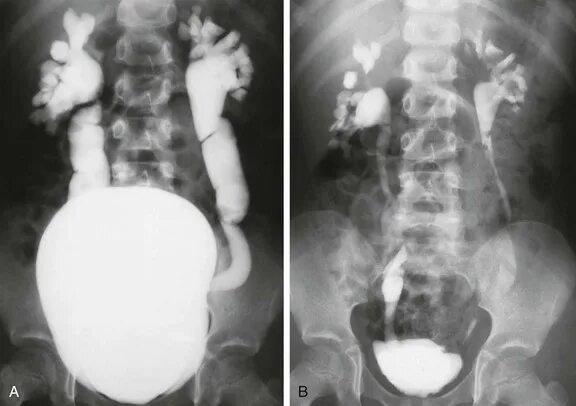

Мегауретер у детей что это